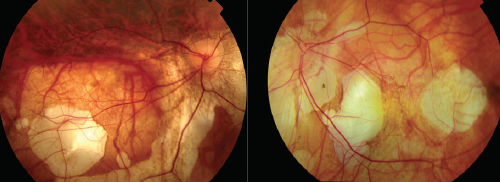

Figure 2. Myopic choroidal neovascularization.

If we study myopic CNV, we can establish three different stages using OCT: active CNV with fluid; fibrotic scar caused by the evolution of the CNV; and atrophy around the fibrotic scar (Figure 2).